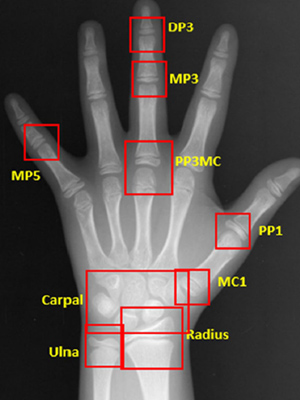

인공지능(AI)을 활용해서 아이들의 성장판 검사를 분석하고,

가장 효과적인 교정 시기를 과학적으로 제안합니다.

이지민 대표원장이 공동 연구한 AI 기반 성장판 분석 논문의 학술적 근거를 바탕으로,

정밀 성장판 검사 프로그램을 통해 성장기 아동의 성장 페이스를 정확히 예측하고

최적의 교정 시기와 치료 계획을 설계합니다.

소아청소년기의 정상적인 성장 여부 판단을 위해

손뼈 엑스레이를 분석하여

높은 정확도의 골연령 판독 결과를 제시합니다.

엑스레이 판독 결과와 키와 몸무게 등의

환자 정보를 함께 평가하여 환자의 예상 신장을 비롯한

유용한 성장 정보를 담은 리포트를 제공합니다.